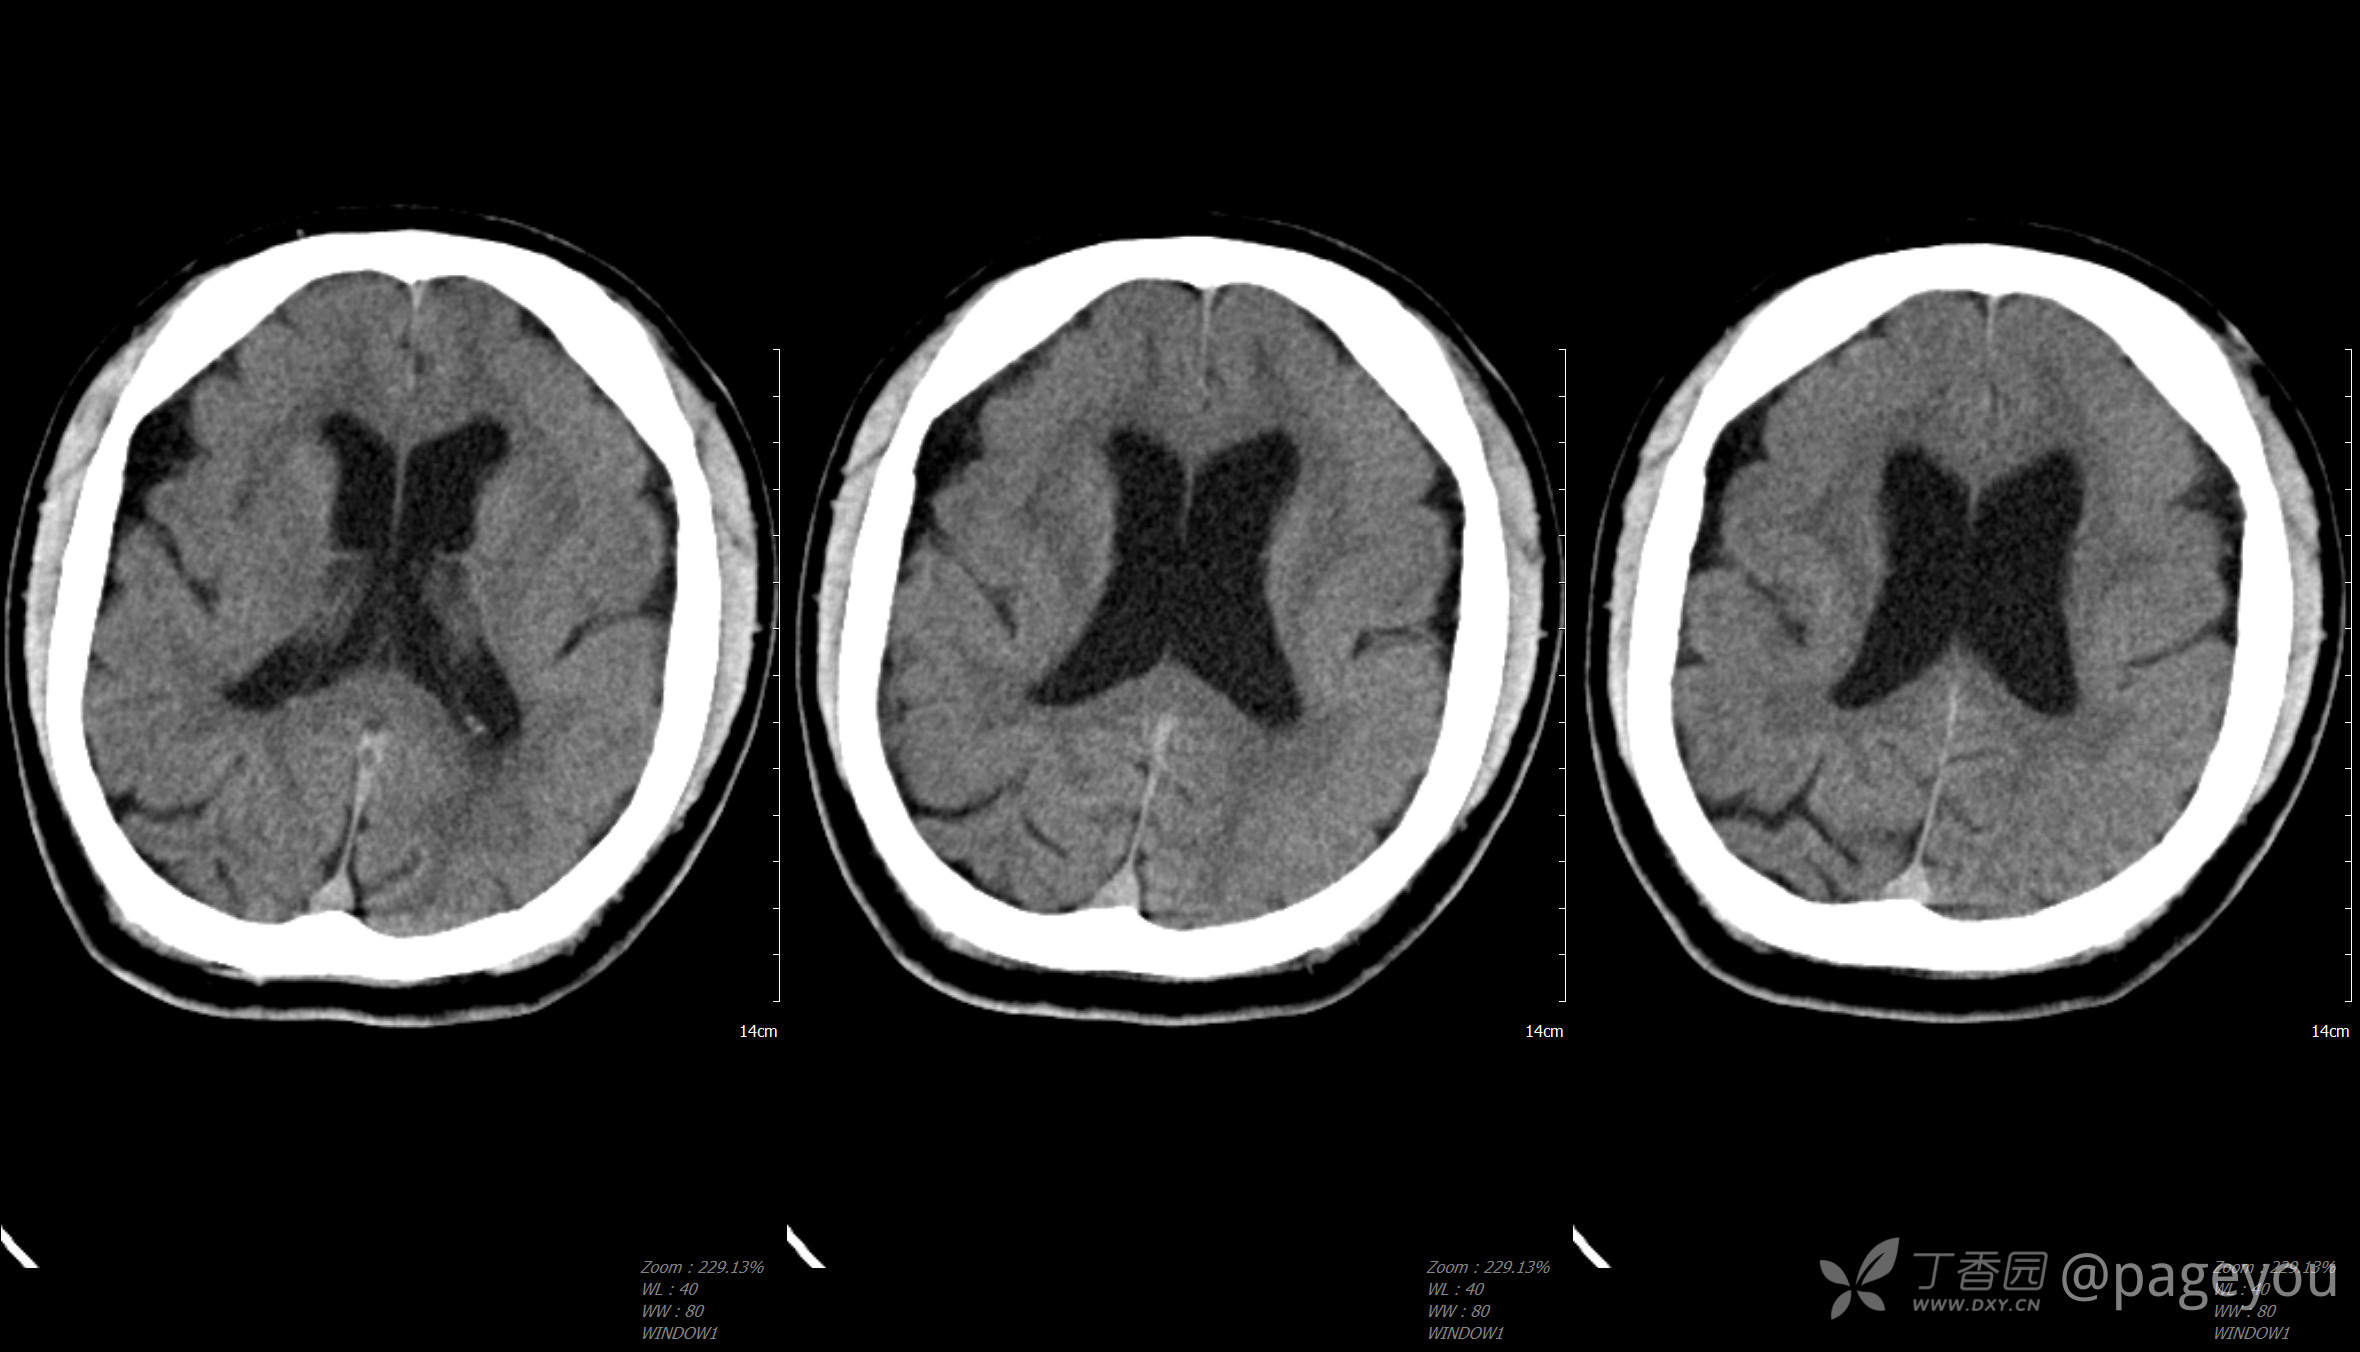

头颅CT: